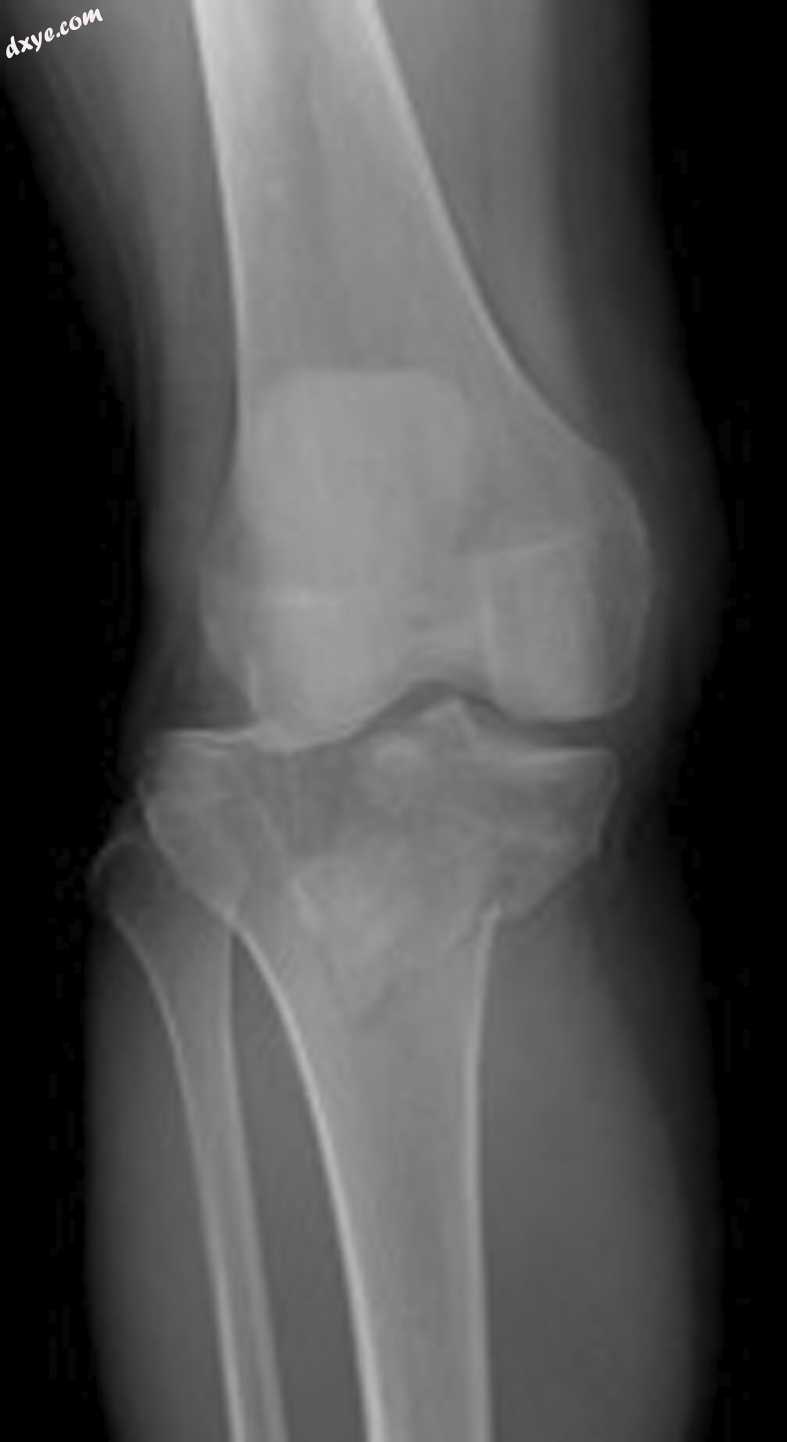

Schatzker IV型被认为是由高能量损伤机制引起的骨折,约占所有胫骨平台骨折的10%。2 骨折线通常穿过内侧胫骨平台并结合 脱位/半脱位膝关节(图1)。 一般认为,Schatzker IV型骨折是导致轴向负荷和膝盖内翻应力的高能量损伤。但是,作者在本研究中讨论的患者出现了穿过胫骨平台外侧的骨折线脱臼 膝关节 - 在作者所谓的'反向Schatzker IV型'骨折模式中(图2)。 据作者所知,这种断裂模式是文献中首次描述的。

图.1

典型的Schatzker IV骨折模式。